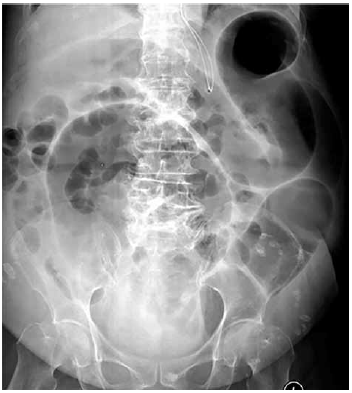

Mulher de 85 anos, com histórico de demência, é tratada com antibiótico oral para infecção urinária. Cerca de 5 dias depois, ela evolui com queda do estado geral e diarreia aquosa. Exame físico: desidratada 3+/4; pressão arterial: 92 x 58 mmHg; frequência cardíaca: 105 bpm; cardiopulmonar sem alteração relevante; abdome: distendido com dor difusa à palpação e redução dos ruídos intestinais; toque retal sem melena ou hematoquezia. Exames séricos: hemoglobina: 12,1 g/dL; leucócitos: 12 200/mm3; plaquetas: 254 000/mm3; proteína C reativa muito elevada; creatinina: 1,3 mg/dL. Hemoculturas são coletadas, assim como exames fecais. A radiografia de abdome é mostrada a seguir.

Considerando a principal hipótese diagnóstica, além de expansão volêmica, o tratamento inicial recomendado é